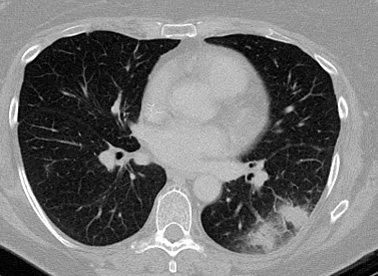

Aspergiloma en una cavidad pulmonar tuberculosa preexistente

De la colección del Dr. P. Chandrasekar; utilizada con autorización

Ver esta imagen en el contexto de la/s siguiente/s sección/es: